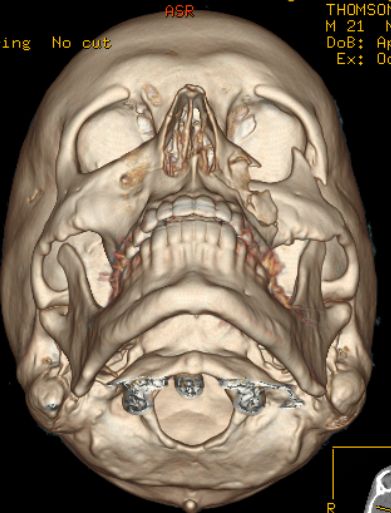

| Danny Thomson estava jogando beisebol com o irmão menor quando de repente este acertou a bola em cheio que veio, a mais de 160 por hora, em direção ao seu rosto. A bolinha acertou sua bochecha esquerda e fez um tamanho de um estrago que precisou de cirurgia para ser reparado. Vejas as imagens: |

a bola rachou o cranio dele, ou eu que vi a tomografia zuada?????

Tomografia 3D show de bola !!!!